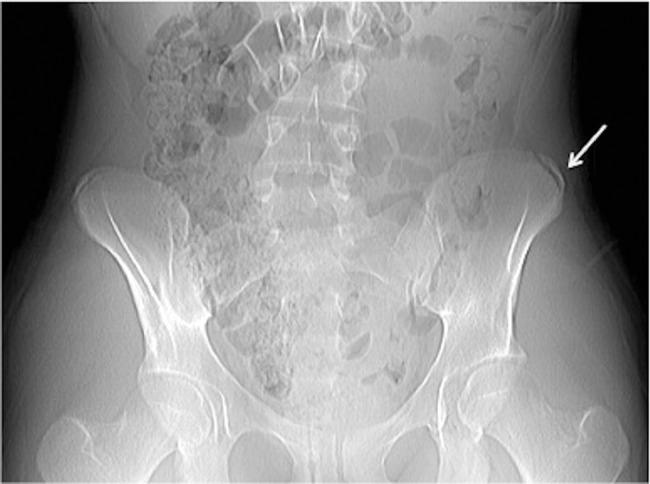

A young cross-country athlete with left thigh pain, and a recent negative MRI of the left hip was referred to nuclear medicine for bone scan imaging. A 3-phase Tc-99m methylene diphosphonate bone scan was performed and revealed left iliac crest apophysis avulsion. This case illustrates that 3-phase bone scan is a great adjunct in the evaluation of sports injuries especially in athletes presenting with vague nonlocalizing symptoms, and prior negative radiographic or MRI imaging.